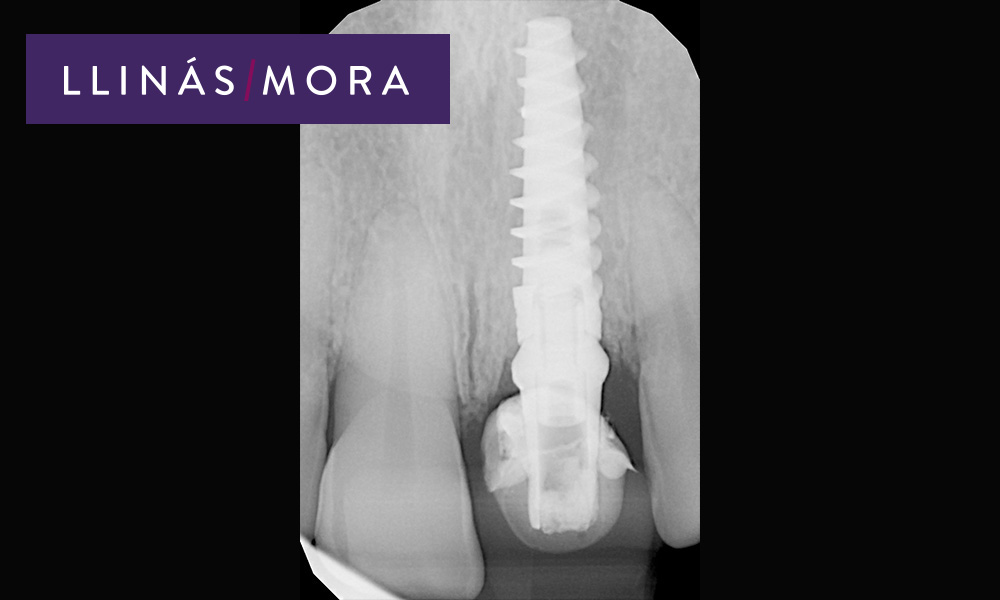

3. Colocación en el mismo acto de implante inmediato, corona provisional fija e injerto de tejido conectivo del paladar.

8. Radiografía del Implante